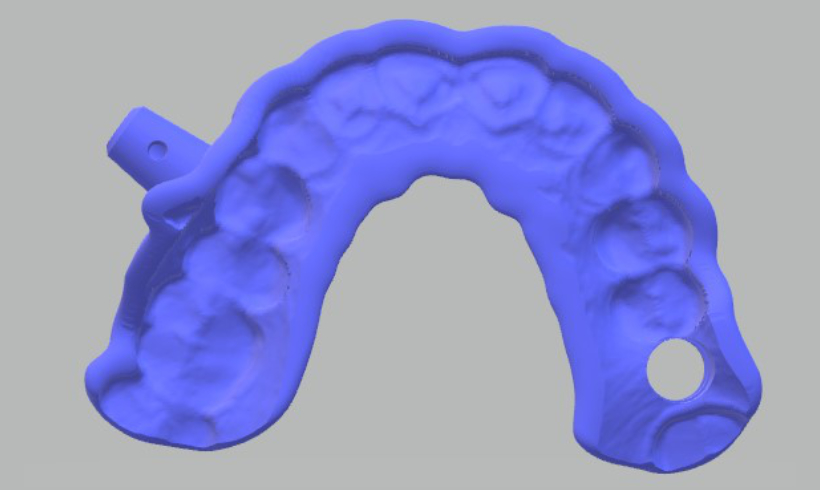

Guías quirúrgicas

Las guías quirúrgicas previa correcta planeación mediante todas nuestras herramientas de diagnóstico clínico y digital, nos permite disminuir el porcentaje de errores clínicos.